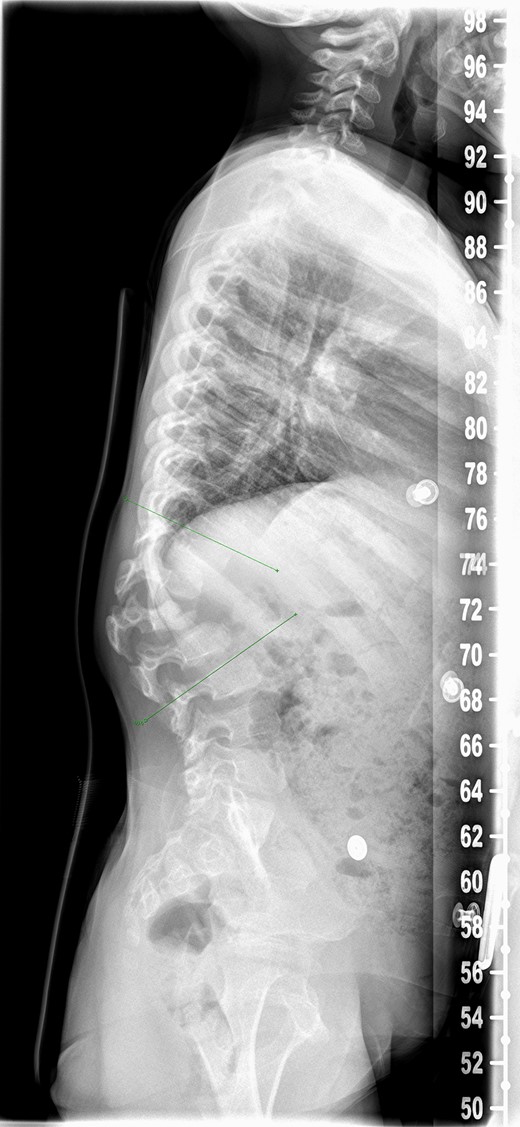

An 8-year-old girl with Mucopolysaccharidosis 1 and high lumbar kyphosis (Fig. 1) was admitted for posterior spinal fusion. Surgery was performed in prone position with multimodality spinal cord monitoring using a posterior midline approach. Spinal fixation was done with pedicle screws from T10 to L3 vertebrae. Spinal osteotomies were performed and kyphosis was corrected. It is the senior surgeon’s preference to augment fusion with i-Factor in order to promote early fusion in this patient group. Two 50 mm i-FactorTM bone graft Flex FR strips were cut along their length, one half was placed medial to the implants over the lamina and the other half placed lateral to the implants in posterolateral gutter. Allograft was placed on top of the strips. Wound was closed in layers leaving behind a drain over the fascia.